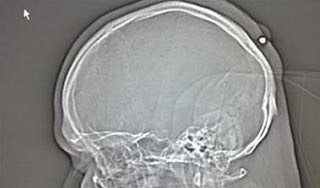

Νομίζοντας λοιπόν ότι πρόκειται για κύστη, ο 35χρονος Πολωνός έβγαλε μια ακτινογραφία, όπου διαπιστώθηκε ότι τόσο καιρό είχε στο πίσω μέρος του κεφαλιού του, καρφωμένη μια σφαίρα.

Η αστυνομία του Bochum που γνωστοποίησε το περιστατικό είπε ότι ο άνδρας θυμήθηκε ότι είχε… πυροβοληθεί στο κεφάλι σε ένα πρωτοχρονιάτικο πάρτι το 2005, αλλά ήταν τόσο μεθυσμένος που ούτε καν του είχε δώσει σημασία!

Το τραύμα γιατρεύτηκε με τον καιρό από μόνο του γύρω από τη σφαίρα κι έτσι ο 35χρονος δεν πολυ νοιάστηκε να τρέξει σε γιατρό για να του τη βγάλουν.

Η εκτίμηση της αστυνομίας είναι ότι η σφαίρα τον βρήκε “καθοδόν” προς το δρόμο, μετά από πυροβολισμό στον αέρα.